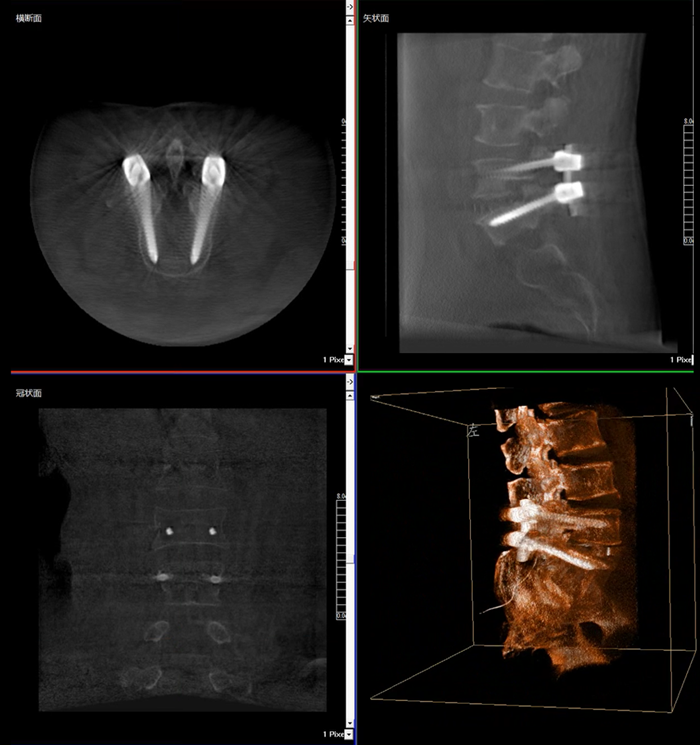

移動式三維C形臂,又稱骨科三維C臂,就是將傳統二維與“類CT模式”相結合的升級版C形臂,能在術中快速地生成橫斷面、矢狀面、冠狀面斷層圖像和三維立體圖像。通過不同方位的斷層圖像,能夠更清晰、完整地顯示椎體及其附件的解剖學結果,直觀地分析病變與周圍組織的立體空間關系,三維斷層成像能夠使手術模擬和手術方案的制定更加準確。

在MPR圖像中,冠狀面、矢狀面和橫斷面的信息大大提高了醫生對于病灶區以及手術效果的判定。

近年來,機器人導航設備在臨床的應用越來越廣泛,而三維影像是機器人導航系統手術執行的基礎,具有地圖定位和效果檢驗的雙重作用,使手術執行更加準確,手術效果驗證更有保障。

普愛醫療在國內率先掌握三維成像技術,繼三維影增C臂后,又推出國產品牌等中心平板移動式三維C形臂——天弓 PLX7500 。天弓配備進口30cm×30cm尺寸動態平板,作為“術中CT”,在手術中快速生成類CT斷層圖像和立體三維圖像,為醫者提供更全面的圖像信息,能夠準確地觀察植入物的情況。如果您對這款移動式三維C形臂產品感興趣的話,可咨詢:400-025-6366。